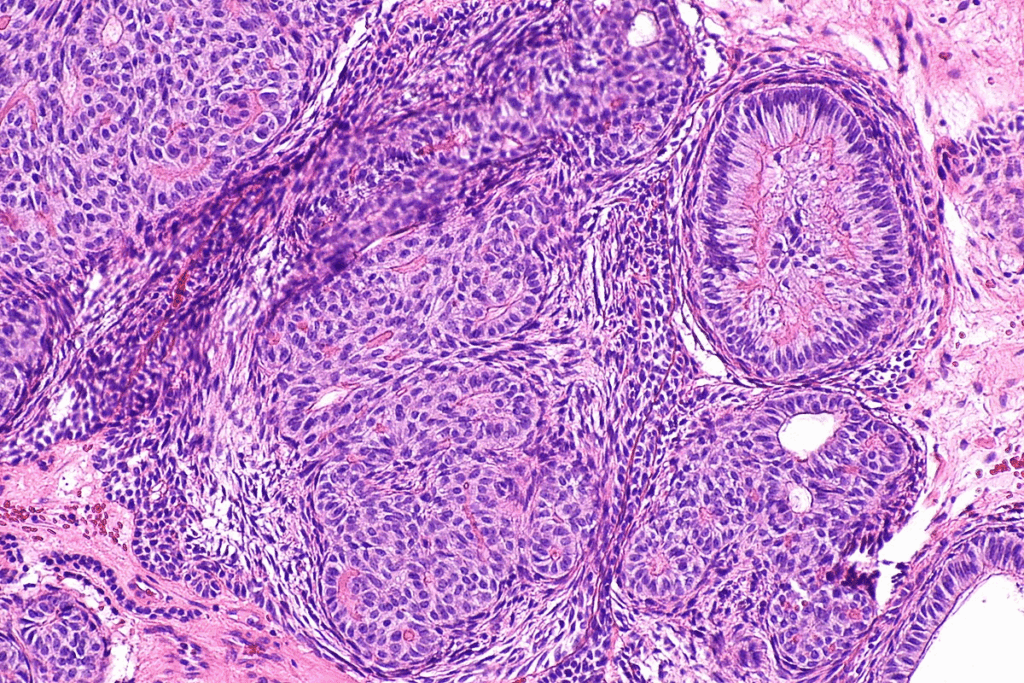

Bladder cancer is divided into several types based on where the cancer starts. The most common type is urothelial carcinoma, also known as transitional cell carcinoma. It starts in the urothelial cells lining the bladder. Other types, like squamous cell carcinoma and adenocarcinoma, affect different cells.

Grading of Bladder Cancer Tumors

Bladder cancer tumors are also graded based on how much they look like normal cells. The grade shows how fast the cancer is likely to grow and spread. Tumors are usually classified as low grade or high grade. Low-grade tumors grow and spread slowly, while high-grade tumors are more aggressive.

It’s key to know the difference between non-muscle-invasive and muscle-invasive bladder cancer. This helps figure out the prognosis and treatment. The main difference is how deep the cancer cells have invaded the bladder wall.

Progression Risk in Non-Muscle-Invasive Bladder Cancer

While NMIBC has a high chance of coming back, the risk of turning into muscle-invasive disease is a big worry. This change is less common but has a worse outlook.

High-grade tumors, CIS, and not responding to treatment are risk factors. Spotting these early helps tailor treatment to stop the cancer from getting worse.